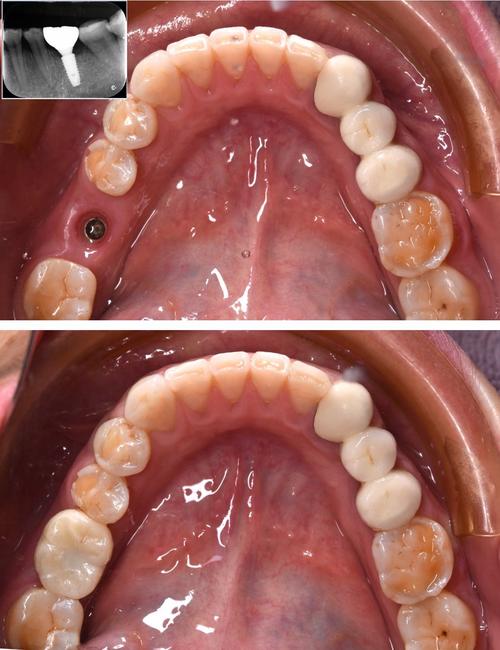

(图片来源网络,侵删)- 专业团队: 口腔科通常拥有经验丰富的种植专科医生或种植团队,医生具备扎实的理论基础和丰富的临床经验。

- 先进设备: 配备口腔CBCT(三维影像)、数字化口内扫描仪、种植机、超声骨刀等先进设备,为精准诊断和微创种植提供支持。

- 主流技术: 常规开展单颗牙种植、多颗牙种植、全口/半口种植(如All-on-4/6技术)、即刻种植、微创种植、骨增量技术(植骨、上颌窦提升)等。